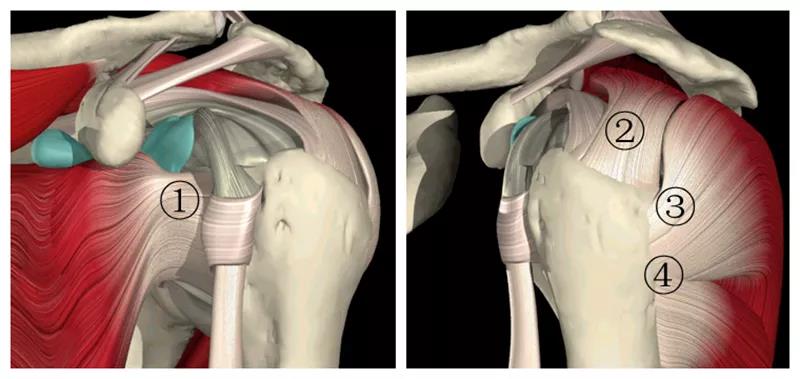

图2 肩袖解剖 1.肩胛下肌 2.冈上肌 3.冈下肌 4.小圆肌